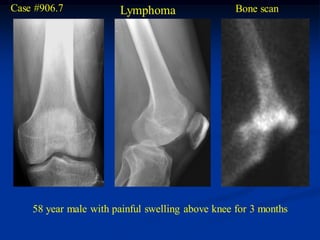

Case #906.7            Lymphoma                   Bone scan

58 year male with painful swelling above knee for 3 months

Cor T-1   T-2 FS

Axial PD   T-2

Sag PD   T-2